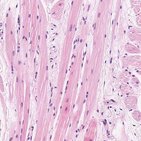

Músculo cardíaco

Tecido muscular esquelético